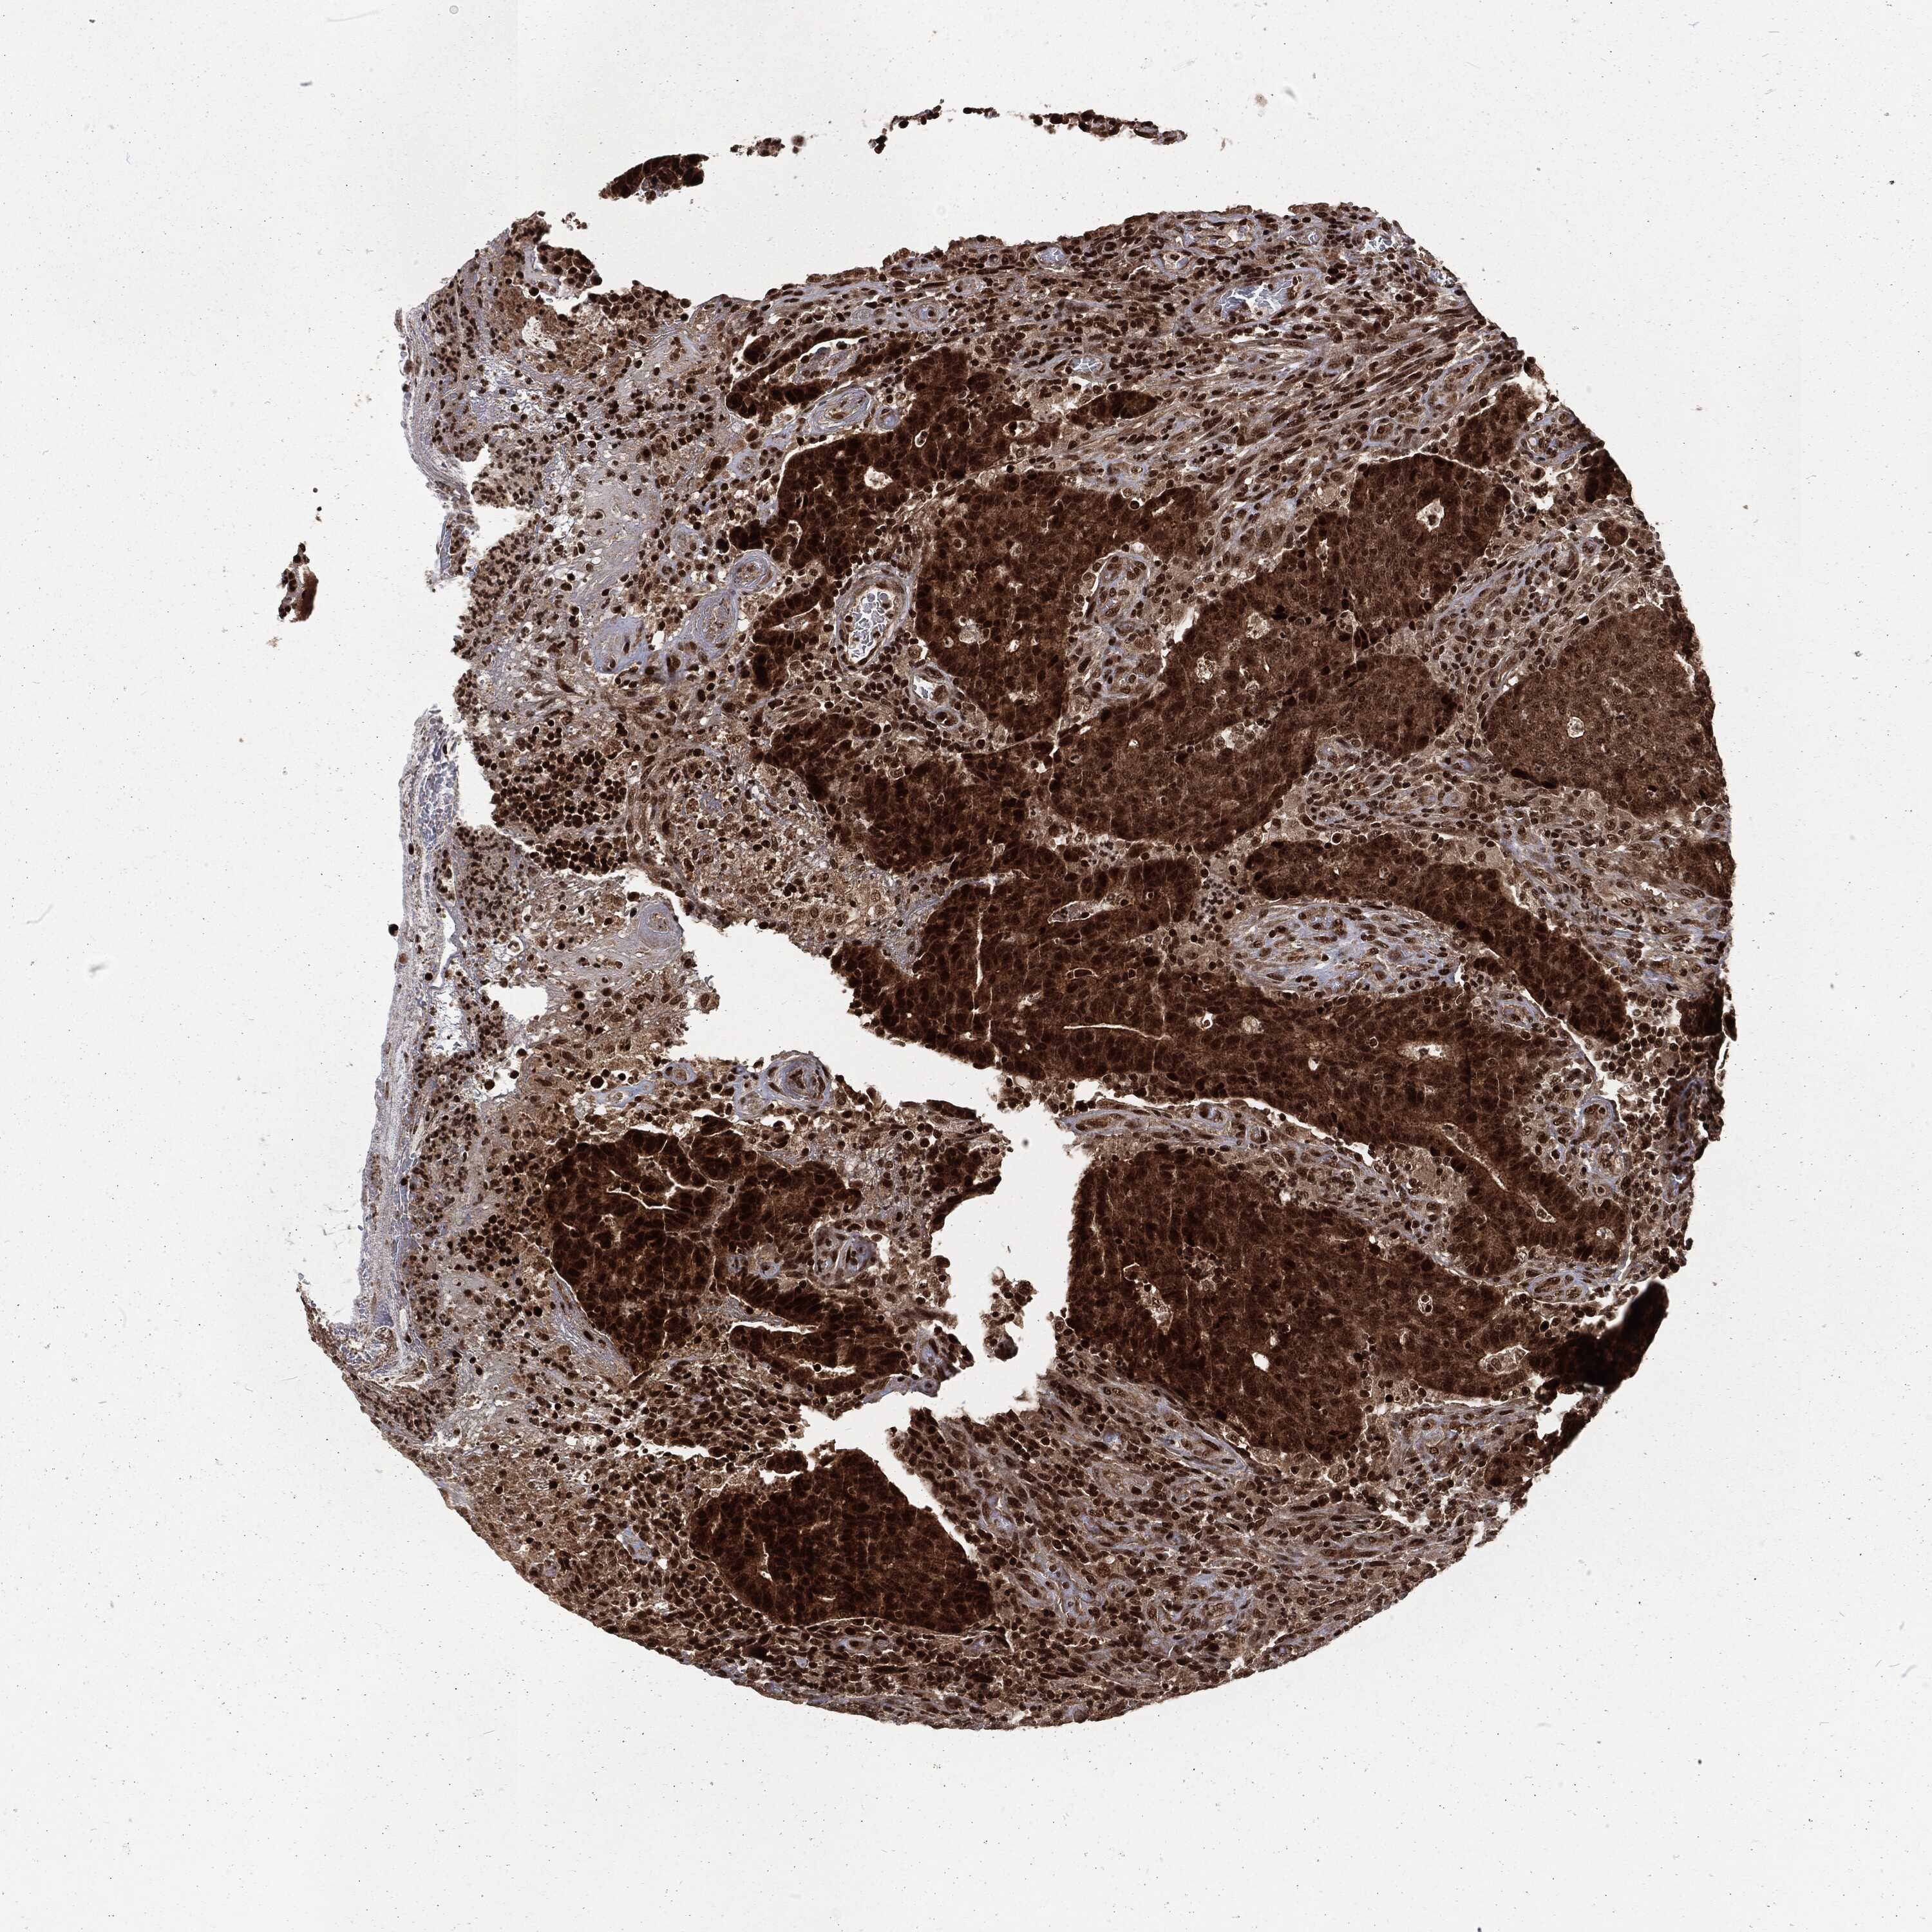

CANCER COLORECTAL CANCER Show tissue menu

COAD TCGA COAD VALIDATION READ TCGA READ VALIDATION PROTEIN COAD CPTAC PROTEIN EXPRESSION

ANTIBODIES

AND

VALIDATION